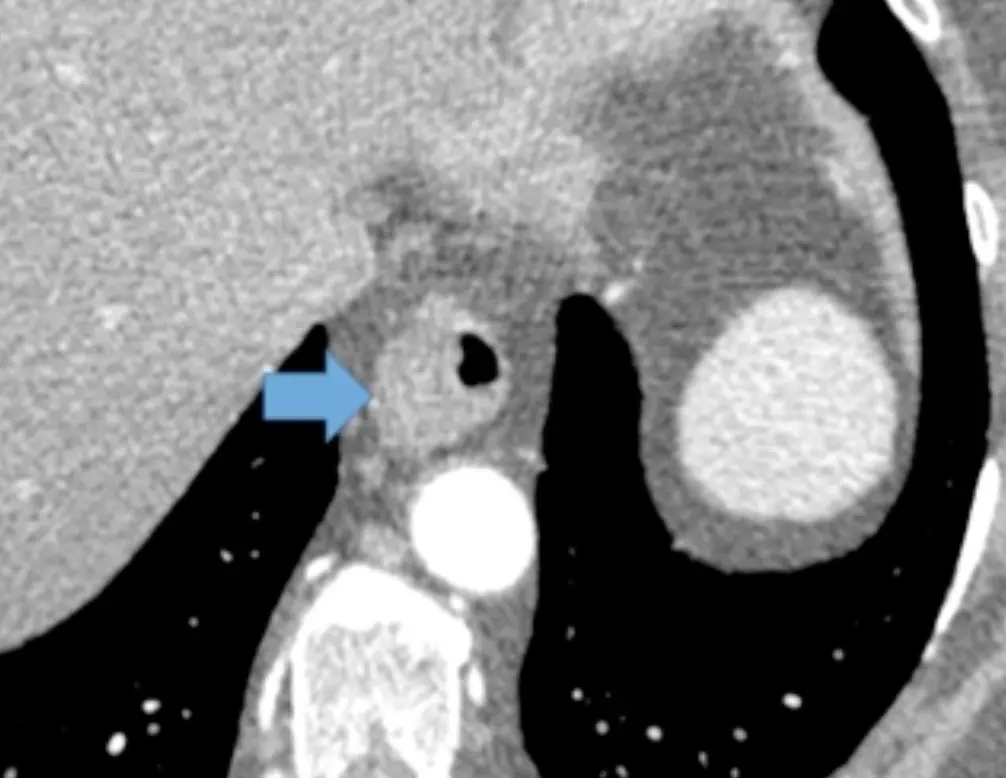

Example: 75 y/o with asymmetric thickening of esophagus prompting endoscopy â Dx: Carcinoma.

Example: 67 year old male with diffuse symmetric thickening of esophagus â Dx: Carcinoma